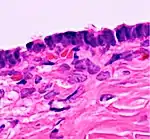

Histopathology

In case an ovarian cyst is surgically removed, a more definite diagnosis can be made by histopathology:

| Cystadenoma | Serous cystadenoma | Cyst lining consisting of a simple epithelium, whose cells may be either:[21]

|